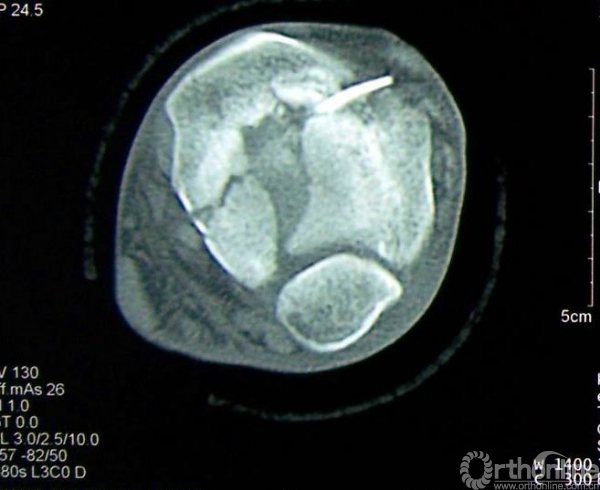

图3 男,35岁,左侧三柱Pilon骨折。

3a.术前正、侧位X线片示胫腓骨远端均为粉碎性骨折;

3b.水平面CT扫描可见属于内侧柱的内踝骨折块、属于中柱的前外侧和后唇骨折块;

3c.术后X线正侧位片示骨折解剖复位并于三柱上分别给予钢板固定,关节面平整。